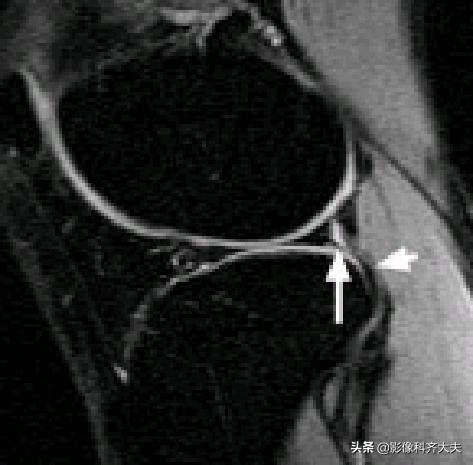

后股板韧带:

内侧半月板后角上隐窝: